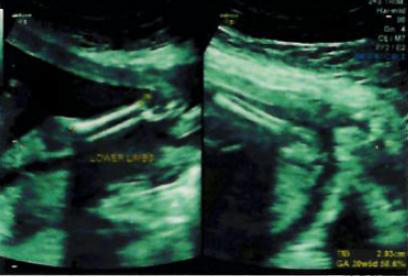

Pls predict gender using attached scans...

Not seeing any gender clues, sorry.